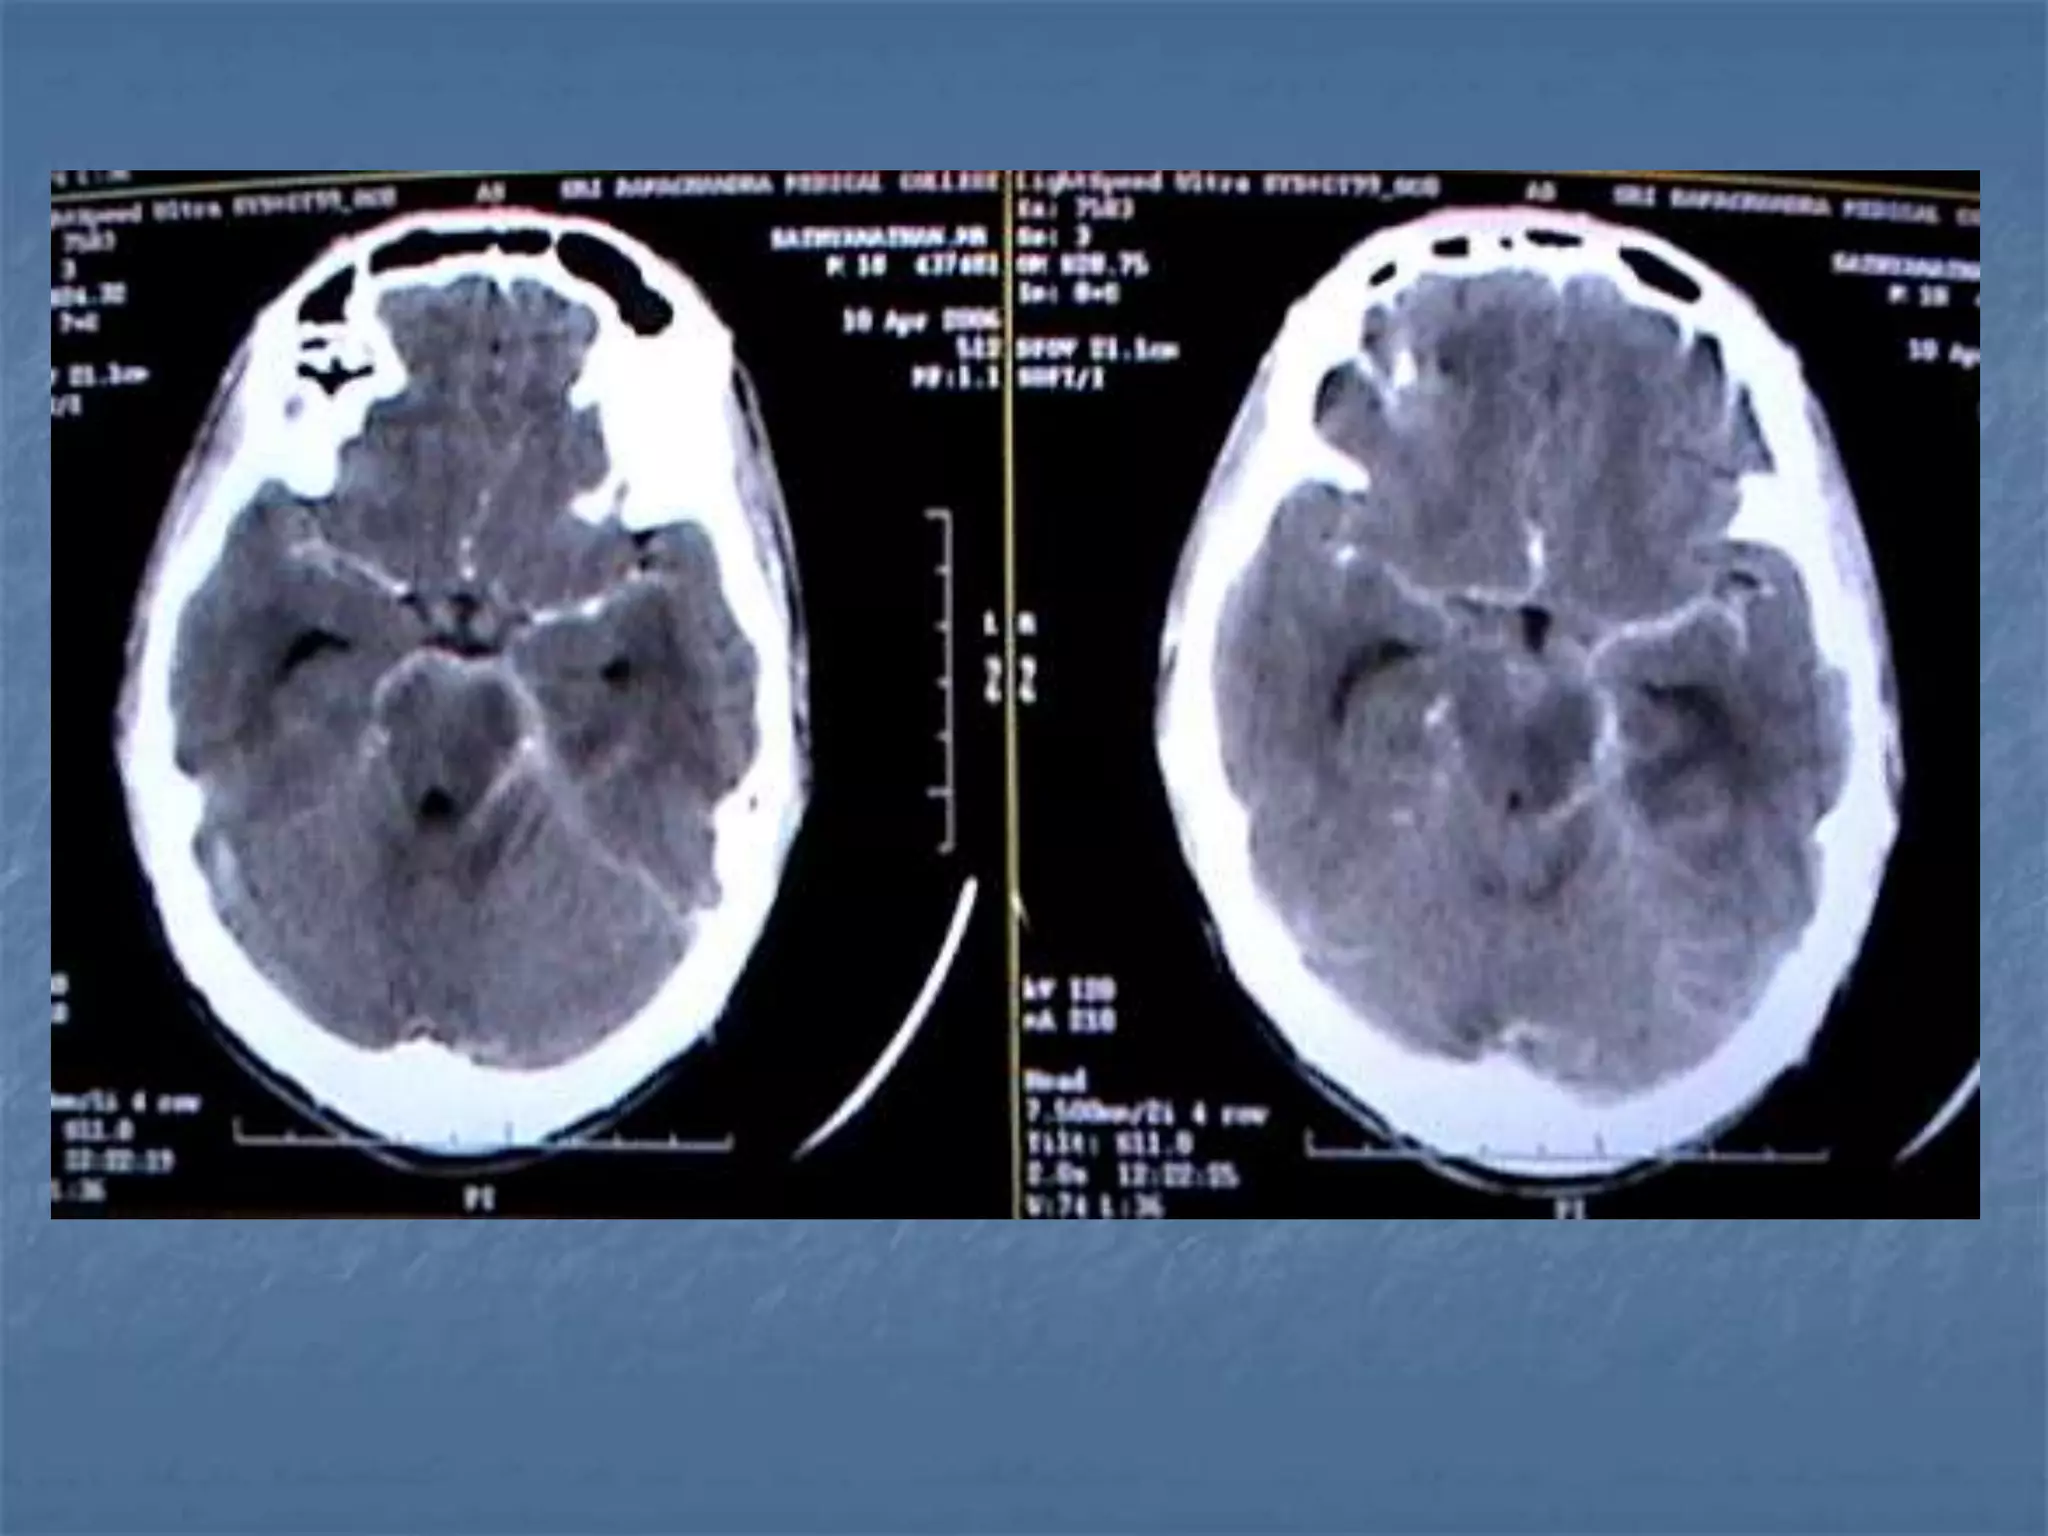

Hypertensive Hemorrhage

 Hypertensive hemorrhage accounts for

approximately 70-90% of non-traumatic primary

intracerebral hemorrhages. It is commonly due to

vasculopathy involving deep penetrating arteries

of the brain. Hypertensive hemorrhage has a

predilection for deep structures including the

thalamus, pons, cerebellum, and basal ganglia,

particularly the putamen and external capsule.

Thus, it often appears as a high-density

hemorrhage in the region of the basal ganglia.

Blood may extend into the ventricular system.

Intraventricular extension of the hematoma is

associated with a poor prognosis.

Haemorrhagic StrokeEtiology

 Hypertension

 Vascular malformation

 Aneurysm

 Trauma

 Amyloid angiopathy

 Tumor

 Coagulopathy

 Hemorrhages can occur in the intraparenchymal,

subarachnoid, intraventricular, subdural and

extradural spaces.

 Location of hypertensive hemorrhage:

Putamen, external capsule, thalamus, pons,

cerebellum, subcortical white matter